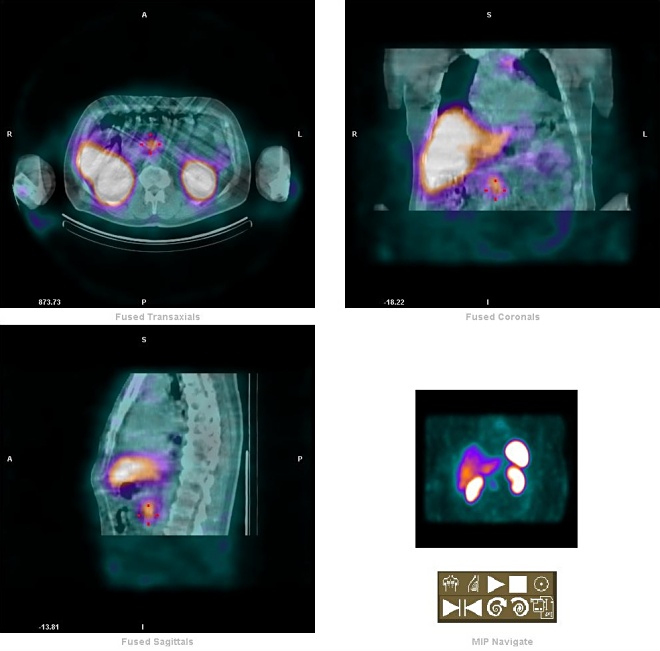

Po aplikaci 111In-oktreotidu (přípravek Octreoscan) zhotoven za 4, 24 hod celotělový

sken, SPECT/CT l hrudníku a břicha. Ložisko zvýšené koncentrace somatostatinových receptorů se zobrazuje v horním, předním mediastinu vlevo retrosternálně, větší velikosti. 2 menší ložiska se zobrazují v oblasti plic. hilu, další ložisko je v nástěnné pleuře

vlevo (cca 5cm nad bráničním úhlem). V abdominální oblasti se zobrazuje zřetelně větší ložisko v oblasti pankreatu, dále v dolní části pravého jaterního laloku ventrálně (5. segment). Lehce vyšší akumulace Rf se zobrazuje i v colon

ascendes.

Závěr: nález svědčí pro diseminaci karcinoidu v horním a předním mediastinu vlevo, v nástěnné pleuře vlevo, v paratracheálních LU vpravo, v

pr. jaterním laloku v obl. 5. segmentu a v tělu pankreatu.

/Obr. 7. abdom. -

pankreas - SPECT /

/Obr. 8. abdom. -

pankreas - CT /

/Obr. 9. abdom. -

pankreas - fuse SPECT-CT /

/Obr. 10. hepar. -

/Obr. 11. hepar. -

/Obr. 12. hepar. -